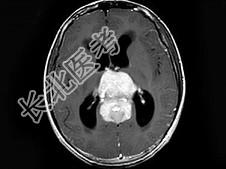

- 单项选择题男,16岁, 头痛数月,MRI平扫及增强扫描如图, 最可能的诊断是 ( )

A、生殖细胞瘤

B、松果体细胞瘤

C、星形细胞瘤

D、室管膜瘤

E、未见异常